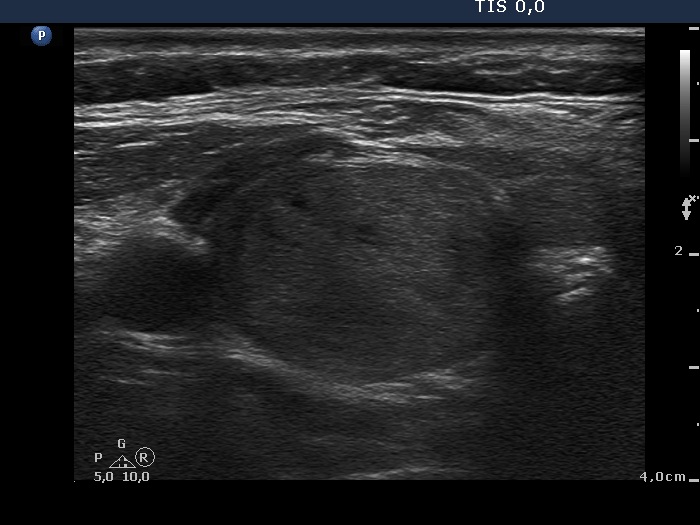

Ultrasonography. Almost the entire right lobe was composed of a minimally hypoechogenic nodule presenting perinodular blood flow. There was a central-type cyst in the left lobe with moderately hypoechogenic solid part. Both the solid and the cystic areas contained large and thick hyperechogenic lines and granules.

Comment. The intranodular hyperechogenic figures are unusually large. The ventral ones correspond correspond to thickened connective tissue and/or to large aggregates of colloid crystals (comet-tail artifacts) while those located in the back wall of the cyst are caused by posterior acoustic enhancement.